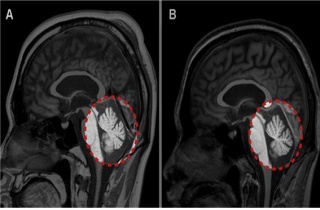

¡°¿­»çº´ÀÌ ¼Ò³ú ¼Õ»ó½ÃÄÑ ¾îÁö·³Áõ À¯¹ß¡±

³ôÀº ±â¿Â°ú ½Àµµ·Î ÀÎÇØ ¿­»çº´(head illness) ȯÀÚ°¡ ±ÞÁõÇϰí ÀÖ´Â °¡¿îµ¥ ¿­»çº´ÀÌ ‘Áö¿¬¼º ¼Ò³ú ¼Õ»ó’À¸·Î ¾î.2017-08-07 11:40:00